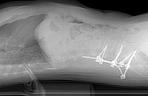

Jej ciało przeszywa wszechogarniający ból. Anna Kulik (37 l.) z Łodzi przeszła już sześć operacji, ale wciąż cierpi. Garściami łyka narkotyczne leki przeciwbólowe, a mimo to czuje, jak śruby zamontowane w jej kręgosłupie się ruszają, uciskają nerwy. Ratunkiem dla niej byłby kolejny zabieg, który kosztuje 60 tys. zł. A na to nie stać biednej rencistki.

Problemy pani Anny zaczęły się od niegroźnej stłuczki samochodowej, do której doszło w 2000 r. Poczuła wtedy ból, a lekarze zdiagnozowali u niej dyskopatię kręgosłupa lędźwiowego. - Żyłam z tym schorzeniem, aż nagle w 2011 r. kręgosłup strzelił, a ból wygiął ciało tak, że chodziłam z nosem na wysokości kolan - wspomina. Trafiła do szpitala na operację, po której było tylko gorzej. W ciągu czterech lat przeszła sześć zabiegów, które nie tylko nie przyniosły poprawy, ale wręcz pogorszyły jej stan. Dziś porusza się na wózku inwalidzkim i bardzo cierpi. Czuje, jak śruby zamontowane w kręgosłupie ocierają się o siebie i uszkadzają nerwy. - Dopada mnie ból, którego nie są w stanie uśmierzyć najsilniejsze leki narkotyczne - opisuje kobieta. - Przyjmując maksymalne dawki środków przeciwbólowych i zwiotczających mięśnie, nie jestem w stanie zasnąć. Biorę 20 tabletek dziennie. Leżę i marzę, aby to już skończyło się raz na zawsze, byle tylko nie cierpieć - dodaje.